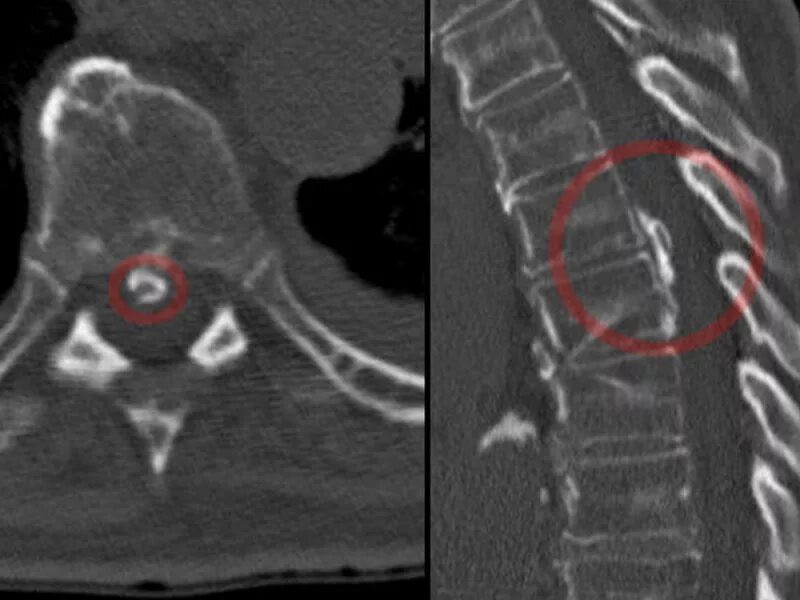

Грыжи на кт